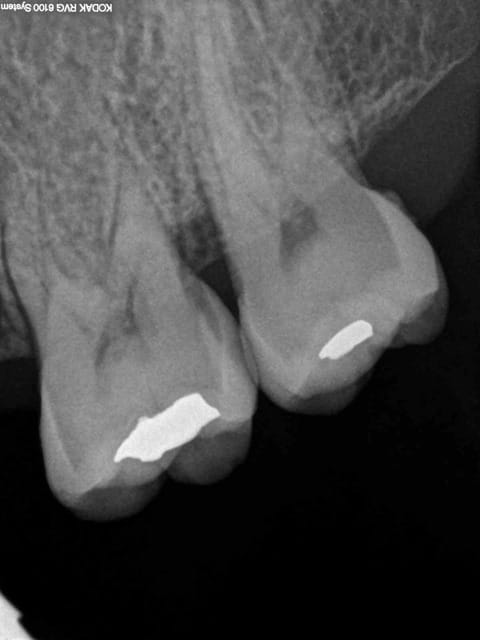

29/09/2014 à 19h28

Je veux pas être rabat-joie mais tu es sûr que tu n'as pas traité la 6 pour rien, au vu de la lésion en mésial de 4, je pencherais pour une fracture de la racine...

Sourire01 écrivait:

-------------------

> Je veux pas être rabat-joie mais tu es sûr que tu n'as pas traité la 6 pour

> rien, au vu de la lésion en mésial de 4, je pencherais pour une fracture de la

> racine...

Douleur +++ au froid sur 26 à sauter au plafond + douleurs spontanées, pas de sensibilité percussion sur 14. Mais ca va chauffer un de ces 4 c'est sur.-))))

Pas grave je virerais 14 + taille crayon sur 23 et 26 vu qu'elle n'est plus reconstituable durablement. -))))))

+ Un petit NR sur 25 ou 24. Macho j'ai bon ? -)))))